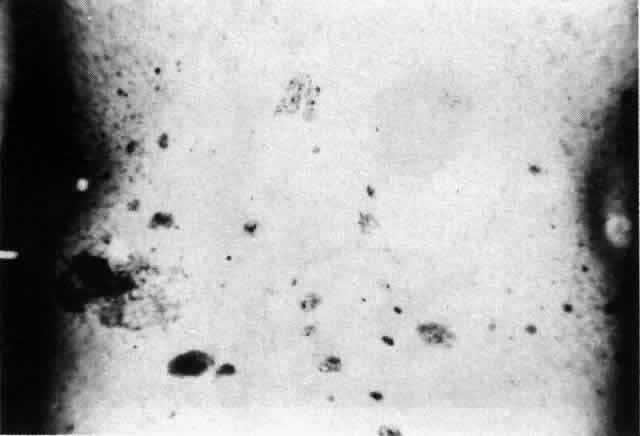

The conjunctival involvement in pemphigus may lead to symblepharon as a result of the formation and rupture of small vesicles. This does not, however, lead to progressive scarring and blindness, as is so often the case in cicatricial pemphigoid (Fig. 4).13

Clinically, the ocular disease in cicatricial pemphigoid (OCP) may present unilaterally in the form of a chronic, recurrent catarrhal conjunctivitis, but it eventually becomes bilateral. Subepithelial fibrosis is characteristic of stage 1 of OCP (Fig. 7). Stage 2 shows fornix foreshortening (Fig. 8), and symblepharon formation is the hallmark of stage 3 (Fig. 9). Stage 4, end-stage disease, is characterized by ankyloblepharon and surface keratinization (Fig. 10). Obstruction of the lacrimal ductules and meibomian gland ducts eventually produces an unstable tear film and progressive sicca syndrome, but it is to be emphasized that OCP is not a dry-eye syndrome until late in the disease course.20 Trichiasis and entropion occur because of the subepithelial fibrosis, with eventual keratopathy, corneal neovascularization, and corneal ulceration and scarring.20

In a series reported from the Mayo Clinic, 21 of 81 patients with cicatricial pemphigoid were blind at the time of the report; 17 of these patients were blind in both eyes. Sixty-two of the 81 patients had ocular involvement; approximately 88% of the 62 patients had the ocular disease bilaterally.18